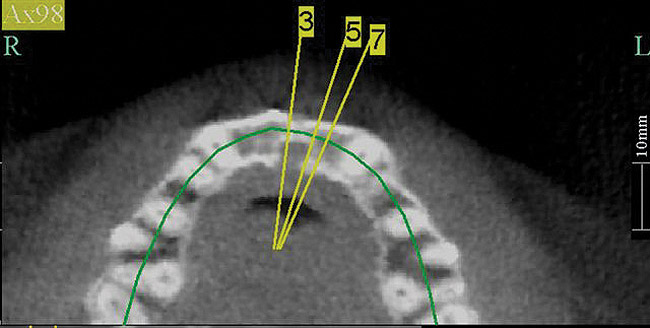

Figure 7  These images summarize the various dimensional assessments that underscore the Rules of Six guidelines, which enable simple planning for uncomplicated single-tooth dental implant therapy: Finding mesiodistal or inter-radicular (Fig 7), buccolingual (Fig 8), and inter-occlusal (Fig 9) distances of 6 mm can assure uncomplicated implant placement and restoration.

Figure 7

Figure 8  These images summarize the various dimensional assessments that underscore the Rules of Six guidelines, which enable simple planning for uncomplicated single-tooth dental implant therapy: Finding mesiodistal or inter-radicular (Fig 7), buccolingual (Fig 8), and inter-occlusal (Fig 9) distances of 6 mm can assure uncomplicated implant placement and restoration.

Figure 8

To summarize the anatomical requirements for the successful placement of a dental implant, the dentoalveolar anatomy of the edentulous site should provide at least 6 mm of bone in three dimensions, and there should be 6 mm of space from the ridge crest to the opposing dentition. The adjacent tooth interproximal contact point should not be more than 6 mm from the bone crest. These anatomical guidelines provide opportunities for reproducible clinical success (Figure 7 through Figure 9).